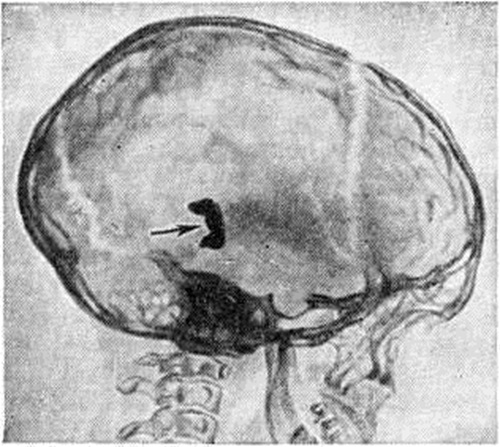

ГидроцефалияГидроцефалия (hydrocephalus; греческий hydor вода + kephale голова; синонимы водянка головного мозга) — состояние, характеризующееся избыточным накоплением цереброспинальной жидкости в желудочках мозга и подоболочечных пространствах. Гидроцефалия является следствием различных заболеваний или травм головного мозга и его оболочек. КлассификацияНаибольшее распространение в СССР получила классификация, предложенная А. А. Арендтом в 1948 год. В ней Гидроцефалия рассматривается в зависимости от времени возникновения, течения, этиологического факторов, локализации и характера нарушения функции ликворного аппарата. По времени возникновения различают врождённую и приобретённую Гидроцефалия, по течению — острую и хроническую. По локализации выделяют наружную и внутреннюю Гидроцефалия При наружной Гидроцефалия имеется избыточное скопление цереброспинальной жидкости преимущественно в субарахноидальных пространствах, при внутренней — в желудочках головного мозга. Нередко наблюдается комбинация внутренней и наружной Гидроцефалия — так называемый общая Гидроцефалия По характеру нарушения функции ликворного аппарата принято различать открытую (сообщающуюся) и закрытую (окклюзионную) Гидроцефалия Открытую Гидроцефалия в свою очередь подразделяют на гиперсекреторную, при которой секреция цереброспинальной жидкости значительно повышена, и арезорбтивную, характеризующуюся нарушением её всасывания. При окклюзионной Гидроцефалия имеется нарушение на различных уровнях оттока цереброспинальной жидкости из желудочков в субарахноидальные пространства в результате спаечного процесса, кист, опухолей и так далее. Встречаются смешанные формы Гидроцефалия, когда окклюзия ликворных путей сочетается с нарушением резорбции или секреции цереброспинальной жидкости. Этиология и патогенезРазличные поражения головного мозга и его оболочек могут привести к Гидроцефалия Чаще всего она наблюдается после инфекционных заболеваний (гнойный эпидемический цереброспинальный менингит, вторичные менингиты и менингоэнцефалиты) и черепно-мозговых травм. Кроме того, Гидроцефалия может возникнуть при затруднении оттока крови из полости черепа (патология венозной системы, тромбоз синусов, сдавление рубцами и спайками отводящих вен), при опухолях, а также при гипертензии, заболеваниях почек и паразитарных поражениях головного мозга. Иногда Гидроцефалия возникает в результате аномалии развития головного и спинного мозга (недоразвитие мозга, мозговые и спинномозговые грыжи и так далее). Вышеперечисленные причины могут привести к нарушению секреции, всасывания или циркуляции цереброспинальной жидкости с последующим развитием Гидроцефалия Патологическая анатомияМорфологически изменения в мозге и оболочках при Гидроцефалия зависят как от основного заболевания, приведшего к Гидроцефалия, так и от длительности повышенного внутричерепного давления. Как правило, наблюдается расширение полостей желудочков, особенно боковых, за счёт увеличения в них количества цереброспинальной жидкости (рисунок 1). Боковые желудочки расширены симметрично как при открытой, так и закрытой Гидроцефалия с окклюзией межжелудочковых отверстий водопровода мозга и апертур IV желудочка (рисунок 2—4). |

Краниография (смотри) позволяет не только поставить диагноз Гидроцефалия, но и определить её форму. При сообщающейся Гидроцефалия, развившейся в раннем детском возрасте, форма черепа шарообразна. Кости свода черепа истончены, рельеф внутренней костной пластинки сглажен (рисунок 6). Отмечается уплощение черепных ямок с углублением передней черепной ямки, расхождение швов черепа к незаращение родничков. Вход в турецкое седло расширен. Для окклюзионной Гидроцефалия характерны выраженные пальцевые вдавления в костях свода черепа, расхождение швов (рисунок 7), расширение диплоических вен, вдавления на кости от поперечного синуса и наличие расширенных эмиссариев. При окклюзии на уровне задней черепной ямки нередко наблюдается отклонение спинки турецкого седла кпереди, истончение её и сужение входа в турецкое седло. При окклюзии в области водопровода мозга дно турецкого седла углублено, спинка его отклонена кзади. При закрытии одного из межжелудочковых отверстий череп имеет асимметричную форму.

Пневмоэнцефалографию с выведением цереброспинальной жидкости применяют при стабилизировавшейся открытой Гидроцефалия для определения величины и формы желудочков, состояния субарахноидальных пространств (смотри Энцефалография). При Гидроцефалия с повышением внутричерепного давления пневмоэнцефалография с выведением цереброспинальной жидкости противопоказана. В этих случаях для определения формы Гидроцефалия и уровня окклюзии применяют пневмоэнцефалографию без выведения цереброспинальной жидкости и с введением небольшого (15—20 сантиметров³) количества воздуха. Прохождение газа в боковые желудочки наблюдается при открытой форме Гидроцефалия Задержка газа на уровне мозжечково-мозговой цистерны свидетельствует об окклюзии в области средней апертуры IV желудочка. Отсутствие газа в III желудочке при его наличии в IV указывает на окклюзию в области водопровода мозга. А задержка воздуха в одном из боковых желудочков наблюдается при окклюзии межжелудочкового отверстия.

Вентрикулография (смотри) показана при выраженной внутричерепной гипертензии и стволовых симптомах, а также в тех случаях, когда предполагается, что Гидроцефалия вызвана опухолью. Она позволяет судить о форме и величине всех отделов желудочков, а также об уровне и характере окклюзии. На вентрикулограммах при открытой Гидроцефалия наблюдается симметричное расширение всех отделов системы желудочков. Контрастное вещество при открытой Гидроцефалия проходит свободно в субарахноидальное пространство спинного мозга. При окклюзии водопровода мозга особенно выражено расширение III желудочка (рисунок 8), отмечается грыжевидное выбухание и опущение его задне-нижних отделов. Поражение верхних или нижних отделов IV желудочка с затруднением оттока цереброспинальной жидкости приводит к расширению всех вышележащих отделов системы желудочков. При непроходимости одного из межжелудочковых отверстий контрастное вещество, введённое в один из боковых желудочков (при целости прозрачной перегородки), не переходит в другой. При окклюзии ликворных путей контрастное вещество задерживается на месте препятствия.